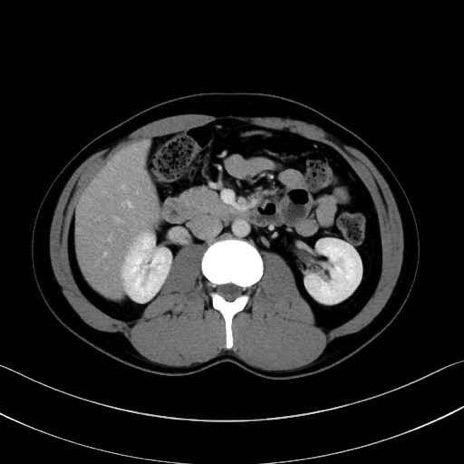

【症例】20歳代 男性 スクリーニング

脾動脈の画像解剖

■起始:典型的には腹腔動脈幹(celiac trunk)から左胃動脈・総肝動脈とともに三分岐し、脾動脈は左後上方へ向かう。

■走行:膵上縁または膵実質背側を蛇行しながら左方へ進み、膵尾部近傍で脾門へ至る。蛇行の程度は個体差が大きい。

■終枝:脾門部で複数の終末枝に分かれ、上極・下極枝や脾門枝群を形成する。胃短動脈群や左胃大網動脈はしばしば脾動脈から分岐する。